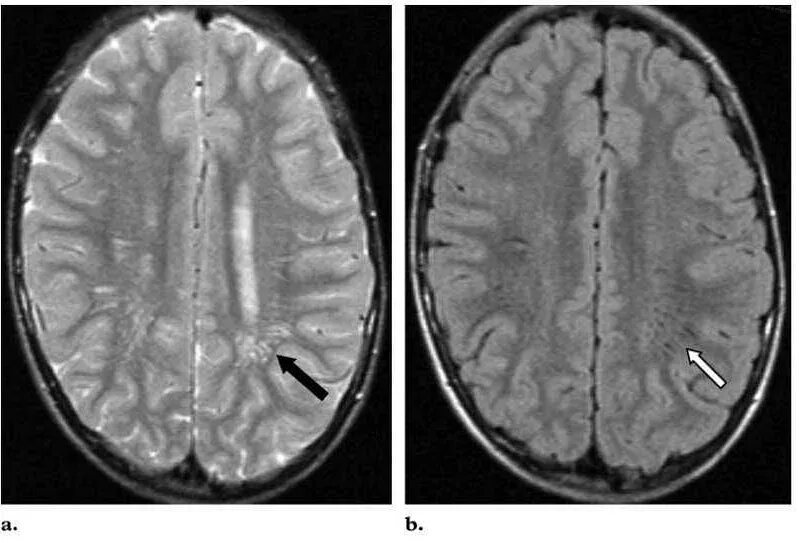

Что значит расширенные периваскулярные пространства